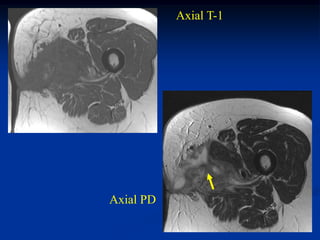

Case #251

11 year male with desmoid foot

Sagittal T-1 MRI

Axial T-1 MRI

Axial T-2 MRI